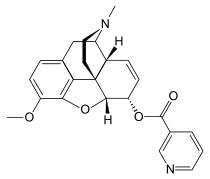

6-nicotinoyldihydromorphine 6-nicotinoyldihydromorphine |

Nicomorphine Nicomorphine | ||